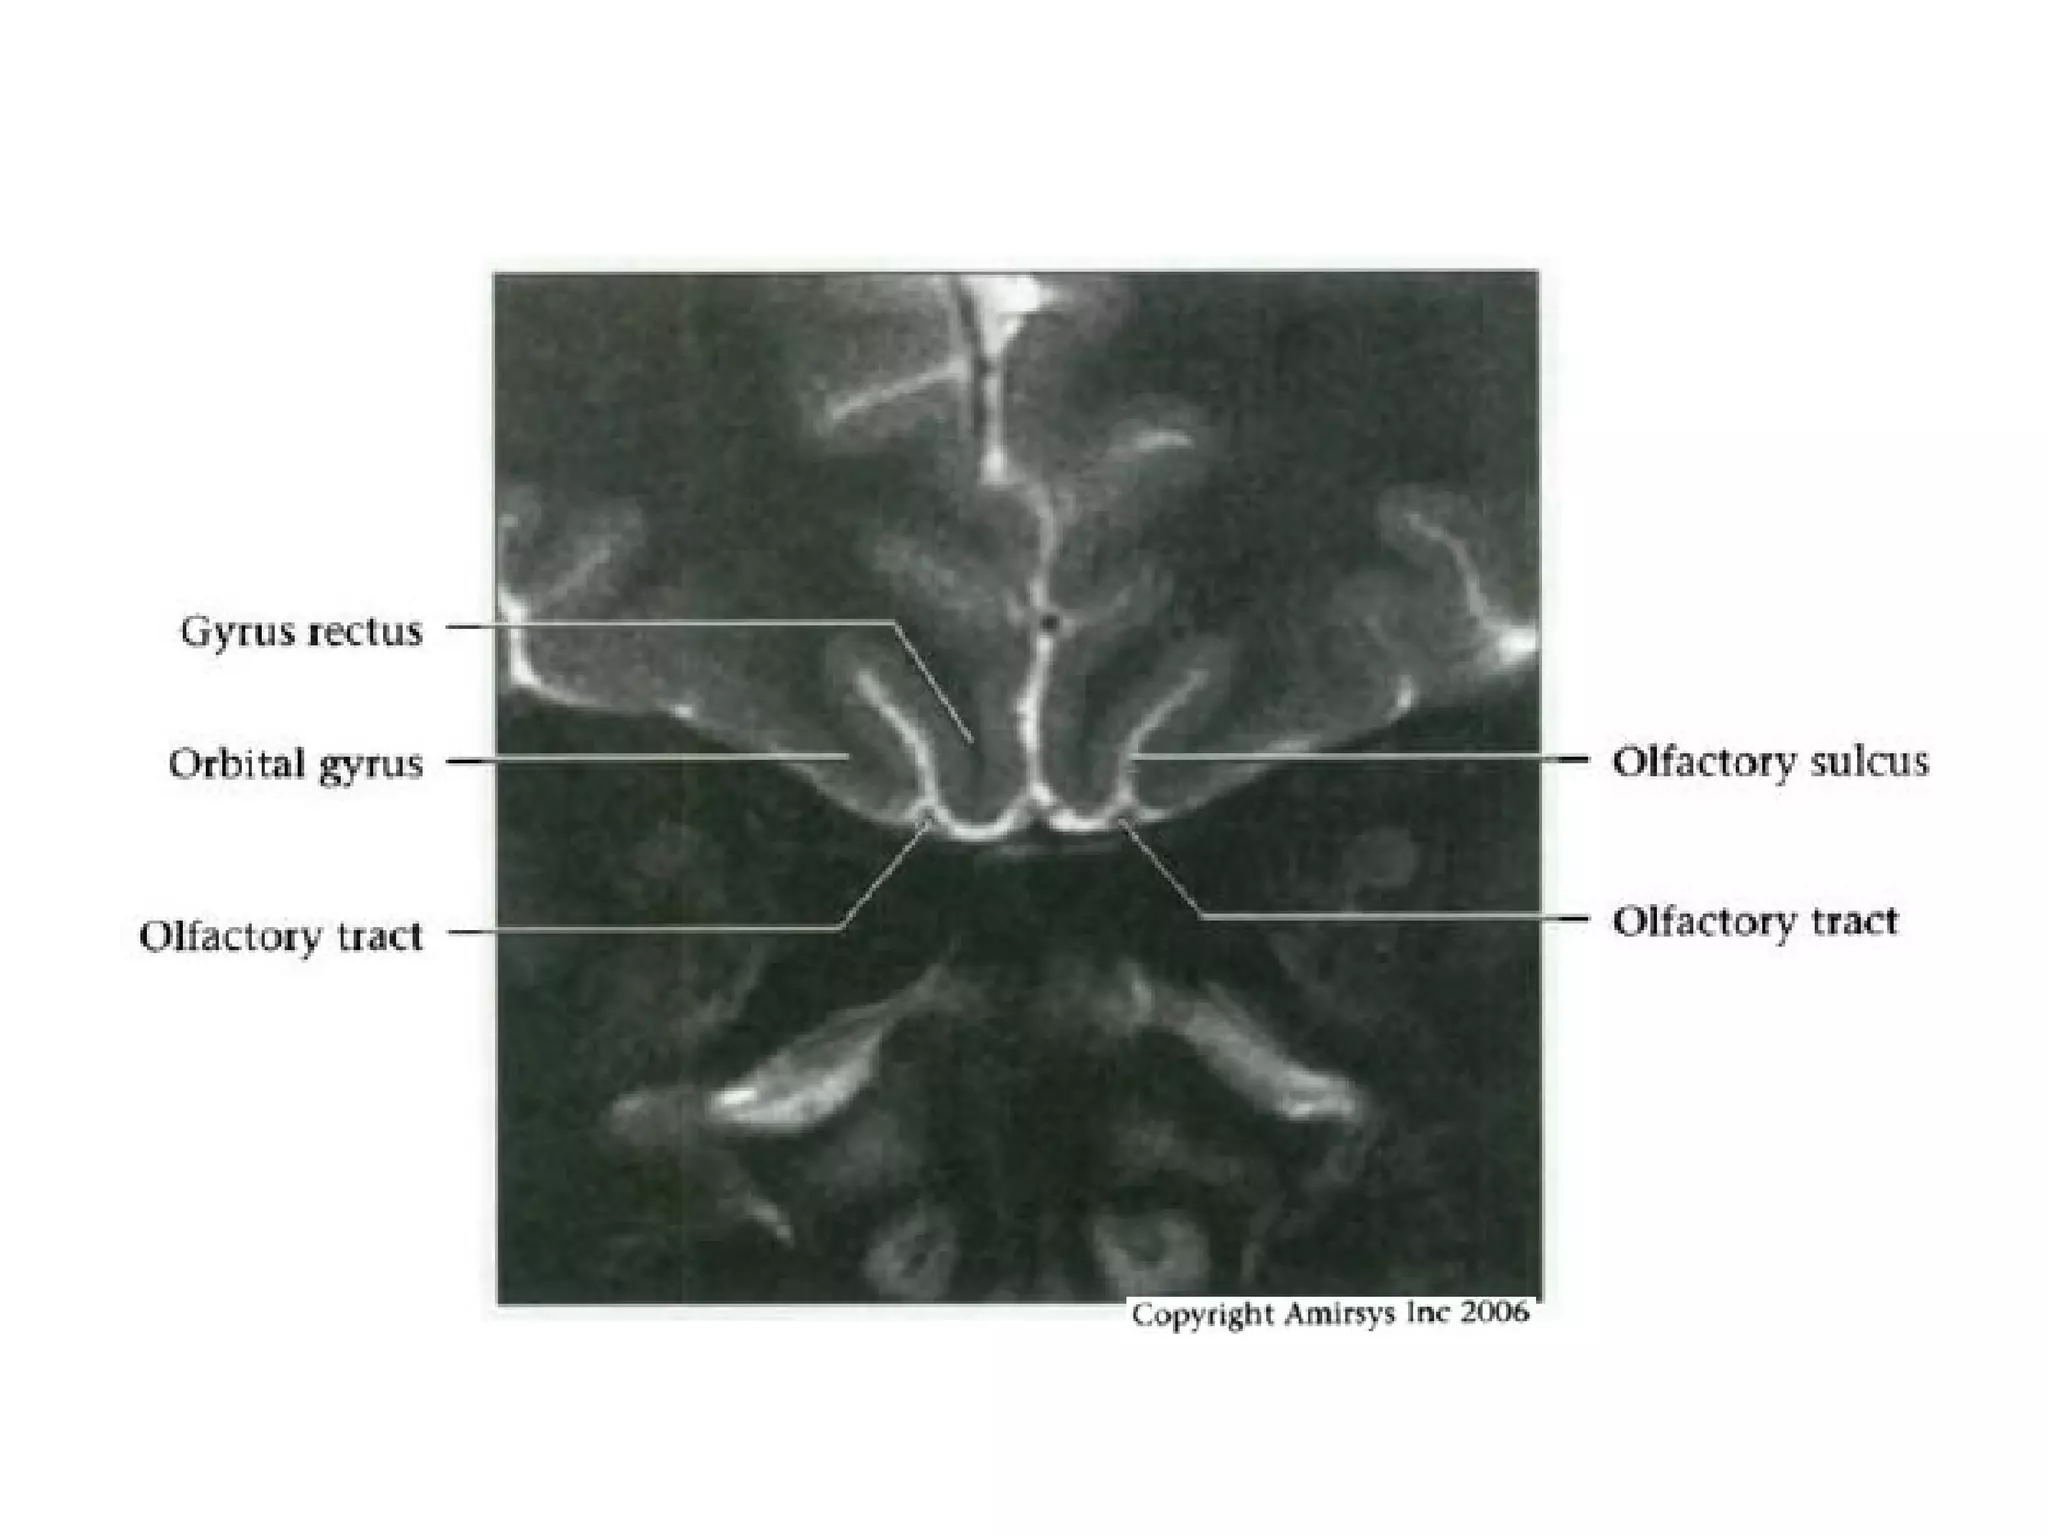

• The nerve then courses posteriorly through the anterior

cranial fossa in the olfactory groove

• Posterior to the olfactory groove, the cisternal segment

of the nerve runs below and between the gyrus rectus

and the medial orbital gyrus

• To avoid confusing the olfactory nerve with the

gyrus rectus on axial images, it is important to

remember that the olfactory nerve is situated

deep in the olfactory groove, inferior to the gyrus

rectus

• Coronal images are easiest to interpret because

the nerves are seen in cross section

Olfactory nerve.

Axial and coronal 0.8-mm-thick SSFP MR images show the olfactory nerve (white arrow)

within the CSF-filled olfactory groove and the optic nerve (black arrow) ringed by

highsignal-intensity CSF within the dural sheath.

Coronal 1.0-mm-thick SSFP MR image shows the cisternal segment of the olfactory

nerve (arrow), which is located inferior to and between the gyrus rectus (r) and the

medialorbital gyrus (o).